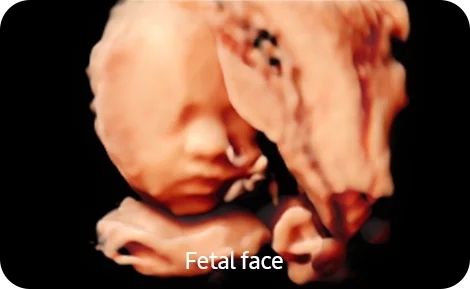

• Smart 4D- Модуль объемного сканирования в реальном времени Smart 4D с расширенным набором инструментов для обработки и представления объемного изображения;

• Realistic Vue- Модуль реконструкции объемного изображения с возможностью перемещения виртуального источника освещения Realistic Vue. Необходим модуль 4D;

• Crystal Vue- Модуль визуализации объемного изображения, с усиленной способностью к контрасту за счет использования различных степеней прозрачности и подсветки структур Crystal Vue;